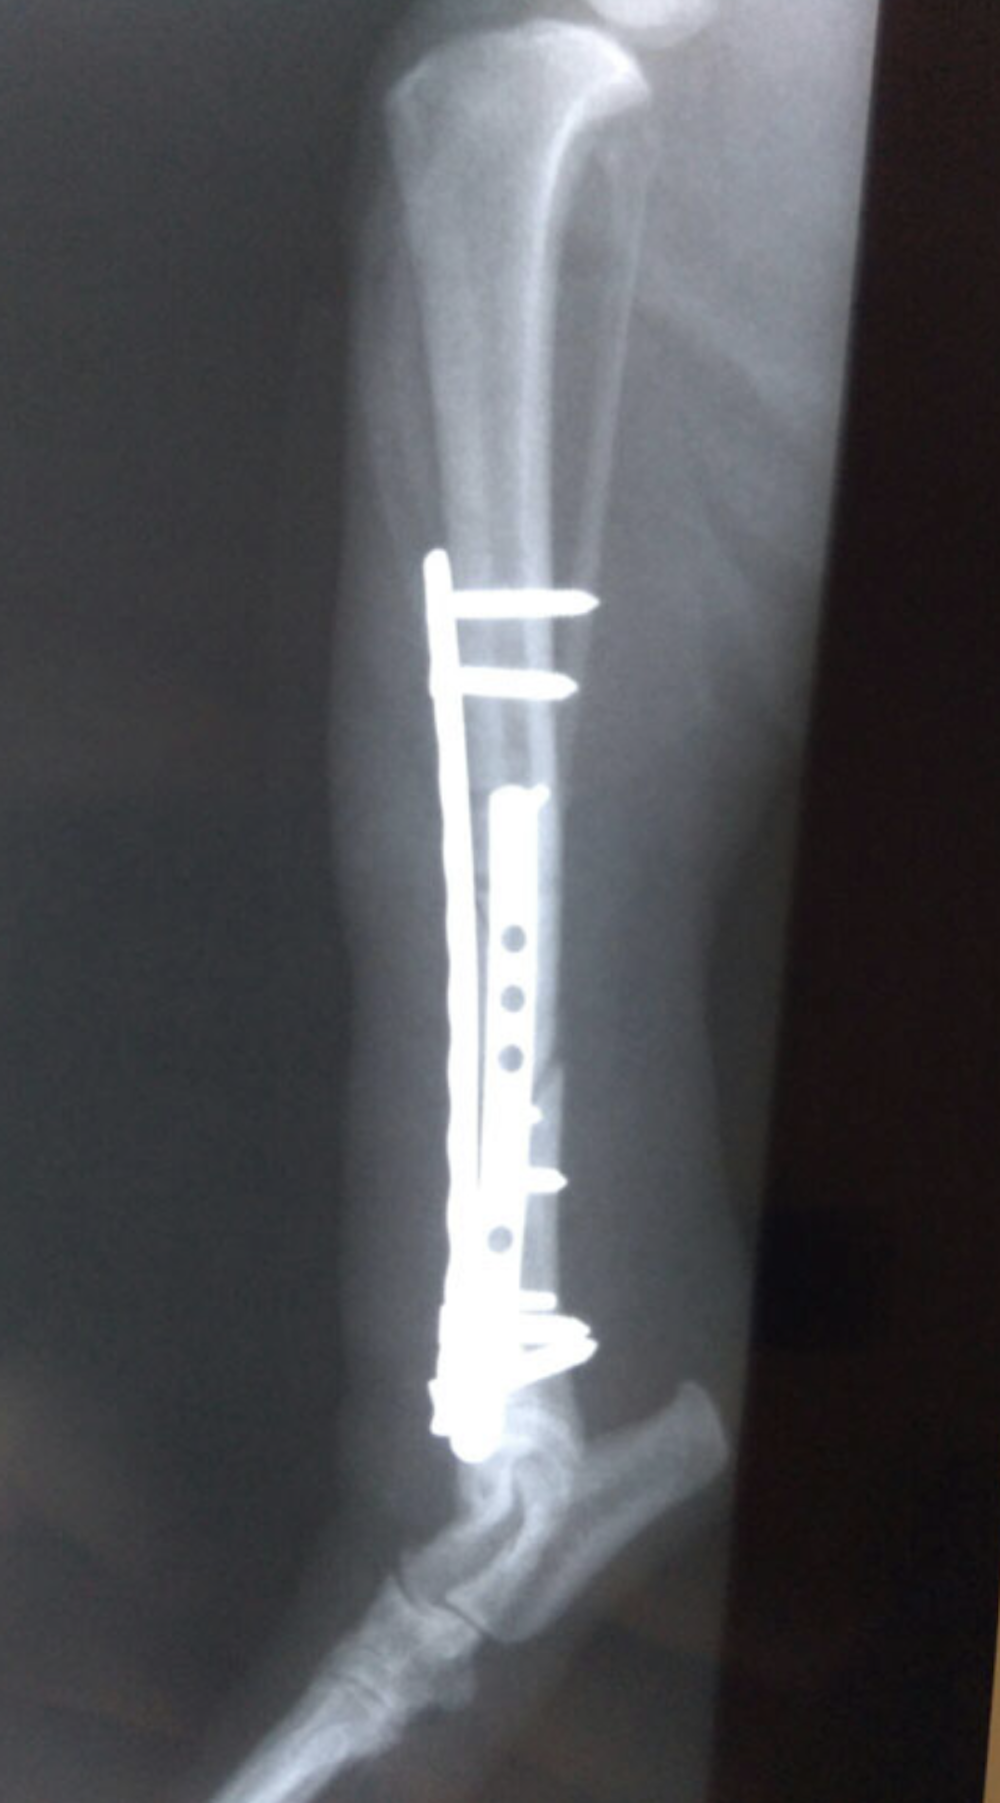

Metatarsal Plating

Example of metatarsal plating.